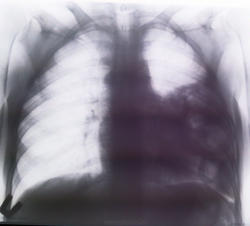

недавно хирурги приводили бабушку с клиникой ЖКБ, холедохолитиазаом, по анамнезу на МРТ около года назад выполненного по поводу образования ворот печени нашли грыжу петель кишечника в грудную полость. Оперативного лечния небыло. У нас Было сделано КТ ОБП с вот такими картинками.

Больная живет несмотря на грыжу.

При врожденном дефекте диафрагмы, до 10 - 15 см, можно долго прожить без клиники непроходимости.

В данном случае, надо полагать, ложная грыжа.

Вместе с дырой в диафрагме может быть незавершённый поворот брыжейки кишечника. Как проистекает траспорт пищи по ЖКТ в таких случаях, - только Богу известно.